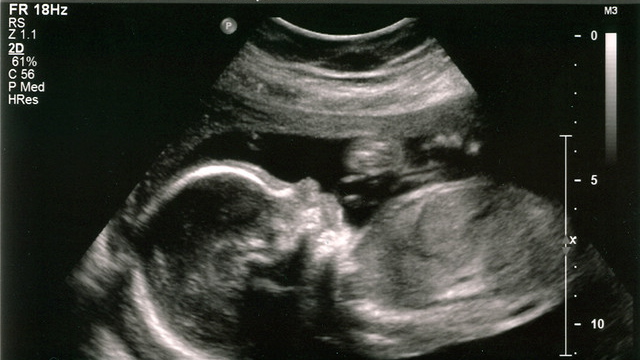

Abort

Jeg har en helt spesiell tante. Hun bor alene, går til jobb hver ukedag, lager mat, er svært glad i besøk og gir bort flotte kort.